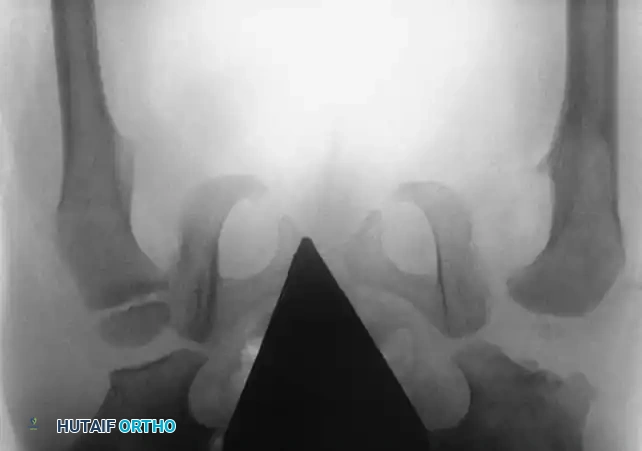

Radiography: Becomes reliable after 4 to 6 months as the ossific nucleus of the femoral head appears. Key radiographic parameters include:

* Hilgenreiner's Line: A horizontal line through the triradiate cartilages.

* Perkins' Line: A vertical line dropped from the lateral margin of the acetabulum, perpendicular to Hilgenreiner's line.

* Shenton's Line: A continuous arc drawn from the medial border of the femoral neck to the superior border of the obturator foramen. Disruption indicates proximal migration.

* Acetabular Index: The angle between Hilgenreiner's line and a line drawn from the triradiate cartilage to the lateral edge of the acetabulum. Normal is <30 degrees in newborns; >35 degrees is highly suspicious for dysplasia.

Radiographic evaluation: Normal hip anatomy (left) versus Dysplastic hip anatomy (right) demonstrating disruption of Shenton's line and an increased acetabular index.

Radiographic appearance following a complex pelvic osteotomy with internal fixation, demonstrating improved center-edge angle and acetabular coverage.